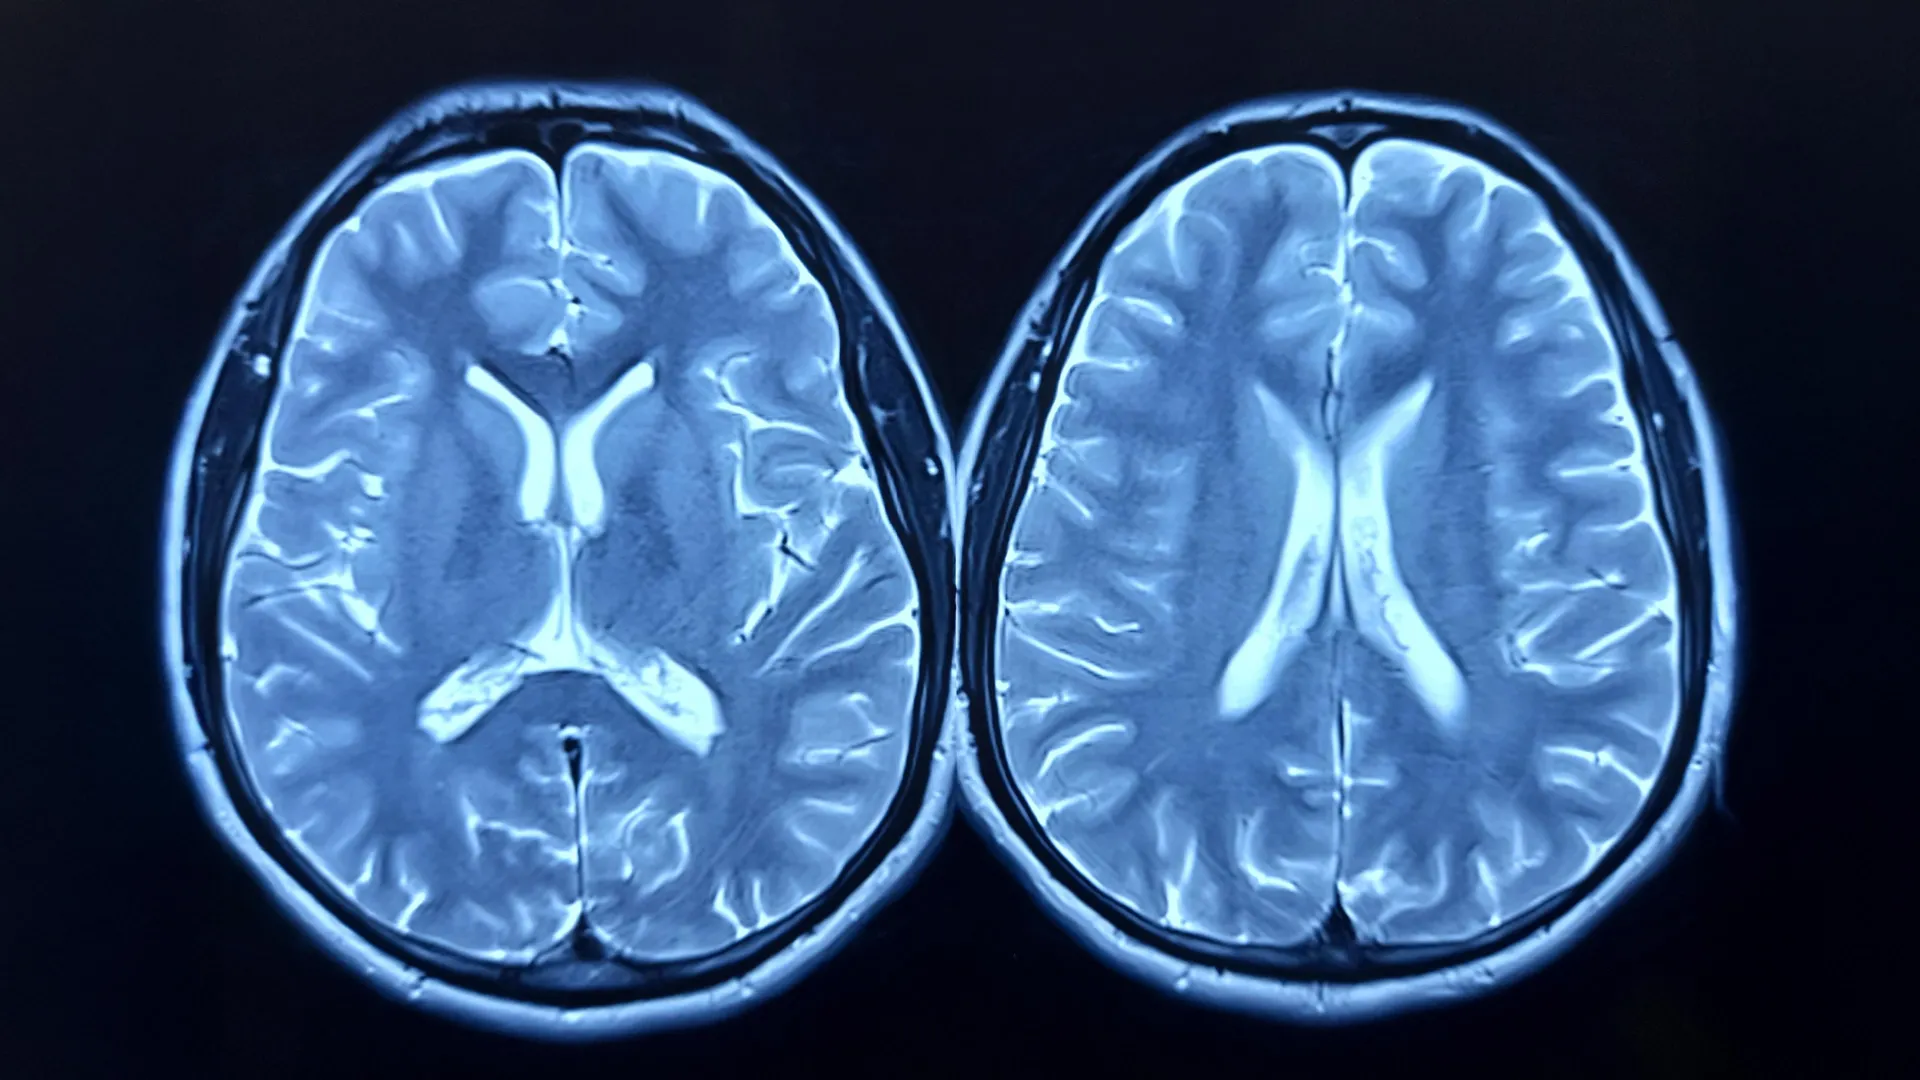

Investigating the concept of "brain age," a metric derived from sophisticated magnetic resonance imaging (MRI) techniques, the study meticulously examined how regular cardiovascular exertion influences this marker of neural aging. Brain age, as determined by MRI, essentially quantifies how old a brain appears relative to an individual’s chronological age. A disparity where the brain’s predicted age significantly exceeds chronological age, often referred to as brain-predicted age difference (brain-PAD), has been previously associated with diminished physical and cognitive capabilities, and a heightened mortality risk.

To quantify the impact of this intervention, researchers employed MRI scans to assess brain structure at the commencement of the study and again after the 12-month period. Concurrently, cardiorespiratory fitness was evaluated through peak oxygen uptake (VO2peak) measurements.

Upon completion of the year-long trial, a discernible divergence in brain age emerged between the two study groups. Individuals who participated in the exercise program exhibited a notable reduction in their brain’s estimated age. In contrast, the control group experienced a slight increase in their brain-predicted age. Quantitatively, the exercise group’s brain-PAD decreased by approximately 0.6 years, signifying a biologically younger appearance of their brains. The control group, conversely, saw their brain age increase by roughly 0.35 years, a change deemed not statistically significant. When directly compared, the exercise group’s brains appeared almost a full year younger than those in the control group.